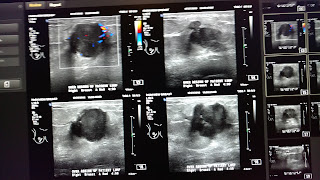

There it was on the screen, and the sweet tech, Hanna (love that it was a Biblical name), had a worried look. I stared at her while she was doing her job: breast ultrasound of my right breast. When I couldn't take it any longer, I asked, "It's pretty bad isn't it?" She nodded. She said something about vascular activity, and "We don't like to see that." I asked what that meant. "It's being fed." Hanna flipped the screen toward me. I said, "Those red and blue dots?" She nodded. She said more things but I was not really listening any more. I was pretty calm, and patting myself on the back for not screaming and overturning medical thingamabobs and running down the hall in the crappy, threadbare gown. Shouldn't I be doing that?